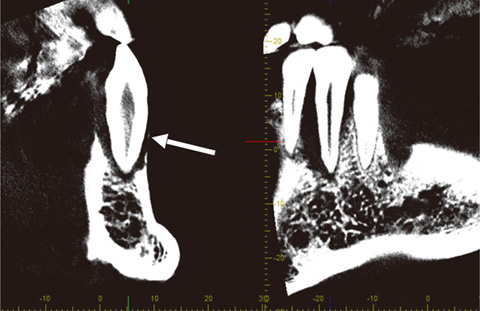

特に、歯根の観察においては、横断像(Z断面)において3断面の交点を歯根の中心(即ち根管)に置き、画面をドラッグしながら微小な回転を行い、断面方向が歯根の頰舌方向、または近遠心方向に一致するように調整すると、他の断面上で歯根の縦方向の断面像が鮮明に表れます(図20、21)。

図20 #37の根管を表示しようとしたが、横断像(左側)において断面の方向(直行した2直線)は歯根断面で斜め方向になっており、歯列平行断像(右側)では根管はうまく表示できていない。

図21 断面方向を歯根断面にそれぞれ垂直方向に調整すると(左側)、根管が鮮明に表示できた(右側)。